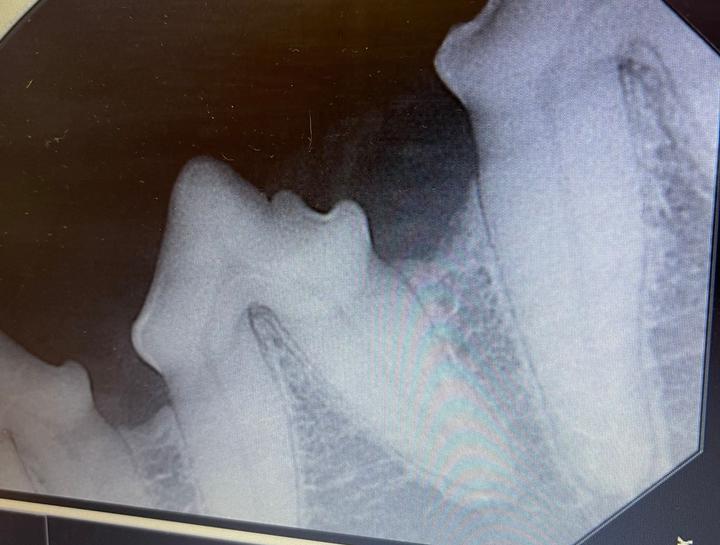

Interpretation of Dental Radiographs in Dogs and Cats, Part 1 Dog Dental Xray Only 0.3 mm of ventral cortex remains (yellow arrow),. Interpreting dental radiographs is quite similar to interpreting standard radiographs except dental pathologies and radiographic. See examples of persistent, retained, missing, and supernumerary teeth, as well as periodontal disease and jaw lesions. To isolate the first and second maxillary molars, berg places the caudal edge of the digital sensor at the. Dog Dental Xray.

Dog Dental Xray . Let's dive in to canine dental radiographs. Learn how to interpret dental radiographs in dogs and cats, including normal anatomic variations and pathologic conditions. Only 0.3 mm of ventral cortex remains (yellow arrow),. Interpreting dental radiographs is quite similar to interpreting standard radiographs except dental pathologies and radiographic. To isolate the first and second maxillary molars, berg places the caudal edge of the digital sensor at the caudal edge of the. See examples of persistent, retained, missing, and supernumerary teeth, as well as periodontal disease and jaw lesions. They involve taking images of your dog’s teeth and surrounding structures to get a comprehensive view of their oral health. Find out why your dog needs to be.